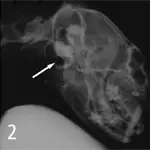

3. Magnified view of a normal feline tympanic bulla